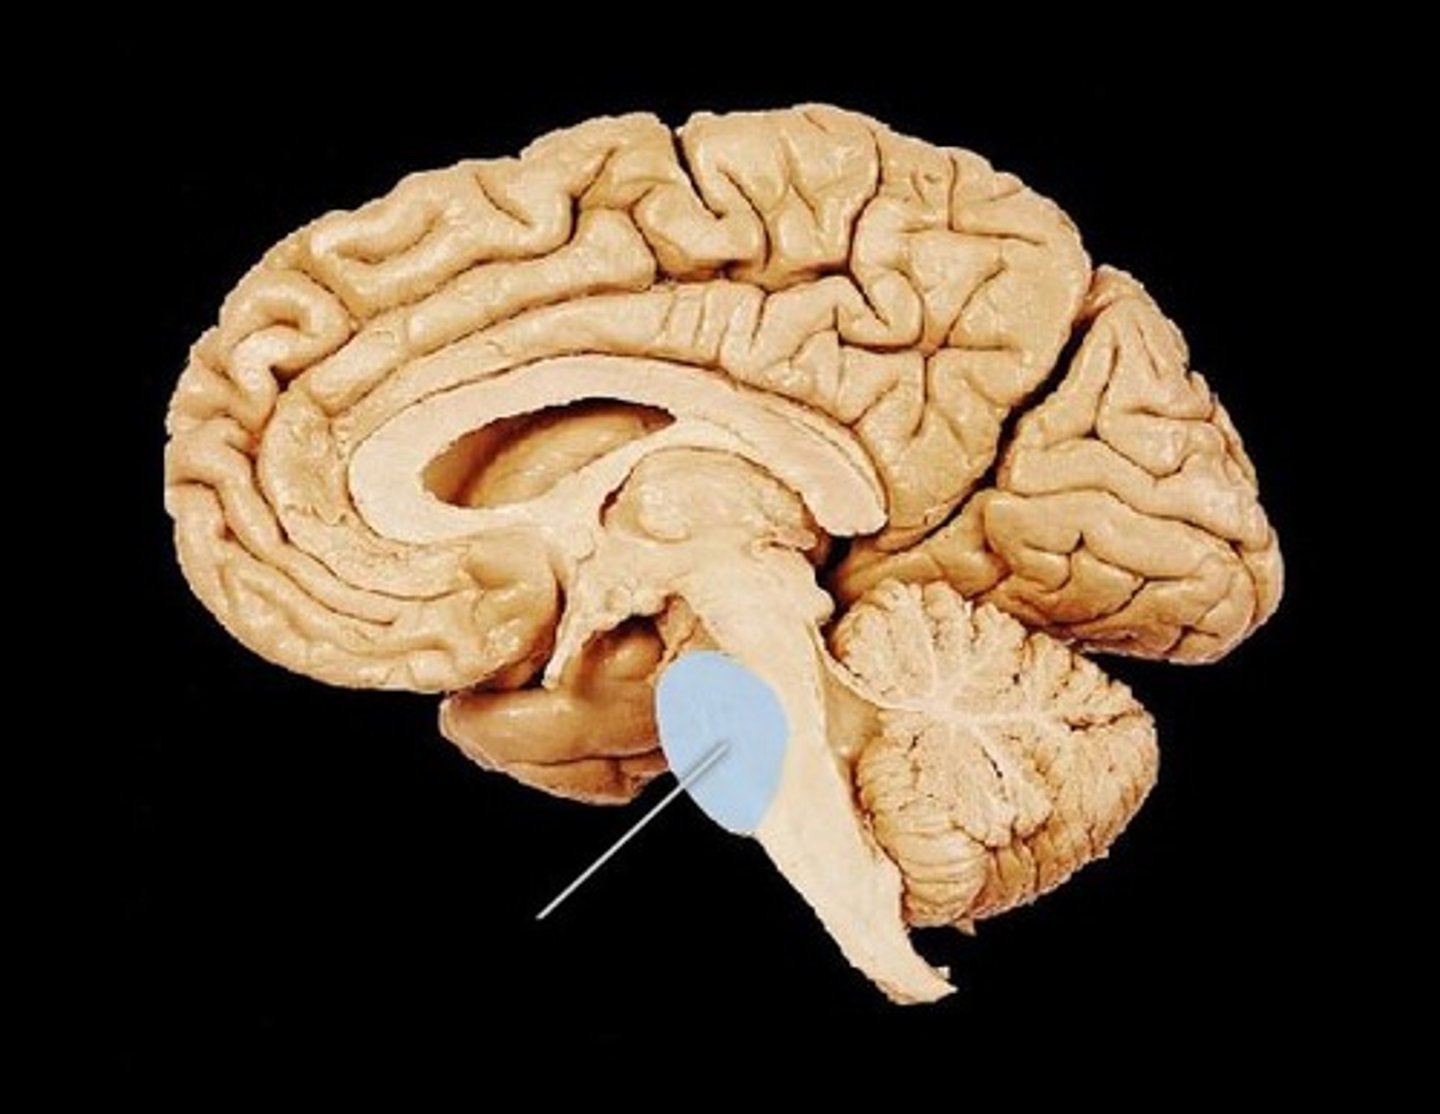

MIdsagittal View of brain

Lateral Ventricle

Third Ventricle

Cerebral Aqueduct

Forth Ventricle

Corpus Callosum

Fornix

Thalamus

Pineal Gland

Superior Colliculi

Inferior Colliculi

Midbrain

Hypothalamus

Cerebral Cortex Gray Matter (nerve cell bodies)

White Matter (myelinated nerve fibers)